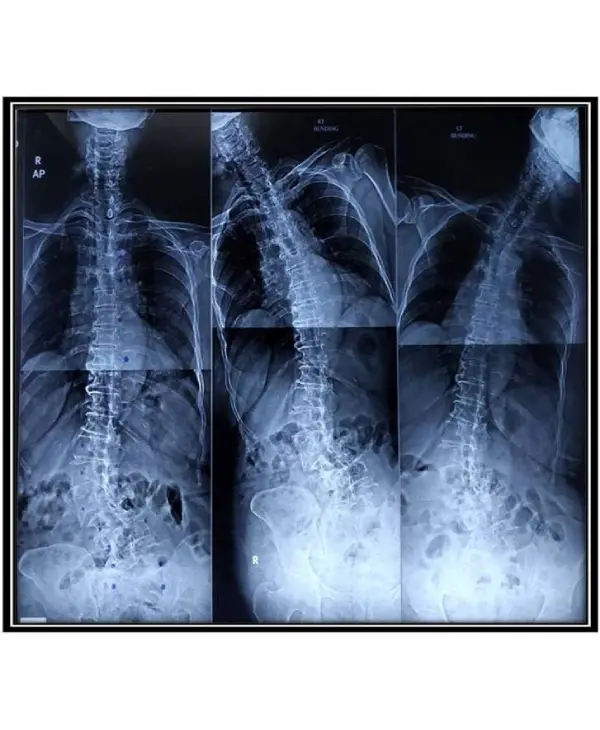

For curves up to 30° periodic follow up with x-rays has to be done. Curves with angle of 30° to 40° needs bracing and close monitoring. Curves more than 40-45° in children with growth potential should be corrected with surgery (posterior instrumented deformity correction and fusion).

12 year old child with cosmetically and functionally disabling deformity in the back

Diagnosis: Congenital scoliosis with hemivertebra and unsegmented bar